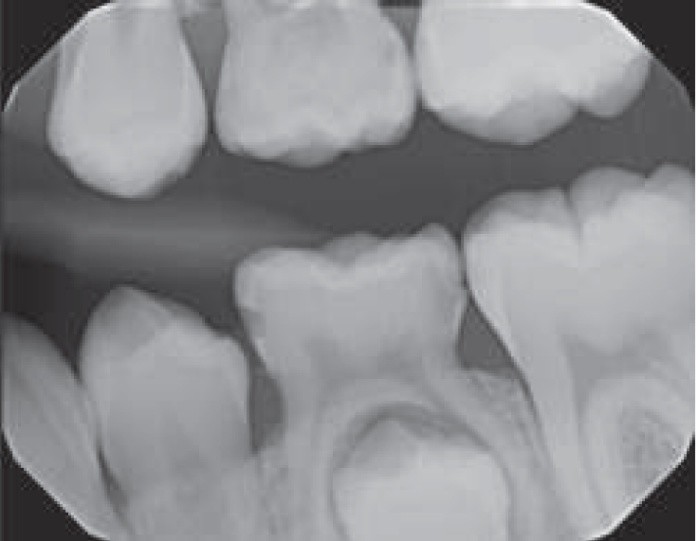

1. (Select ONE OR MORE correct answers)

The radiograph shows evidence of